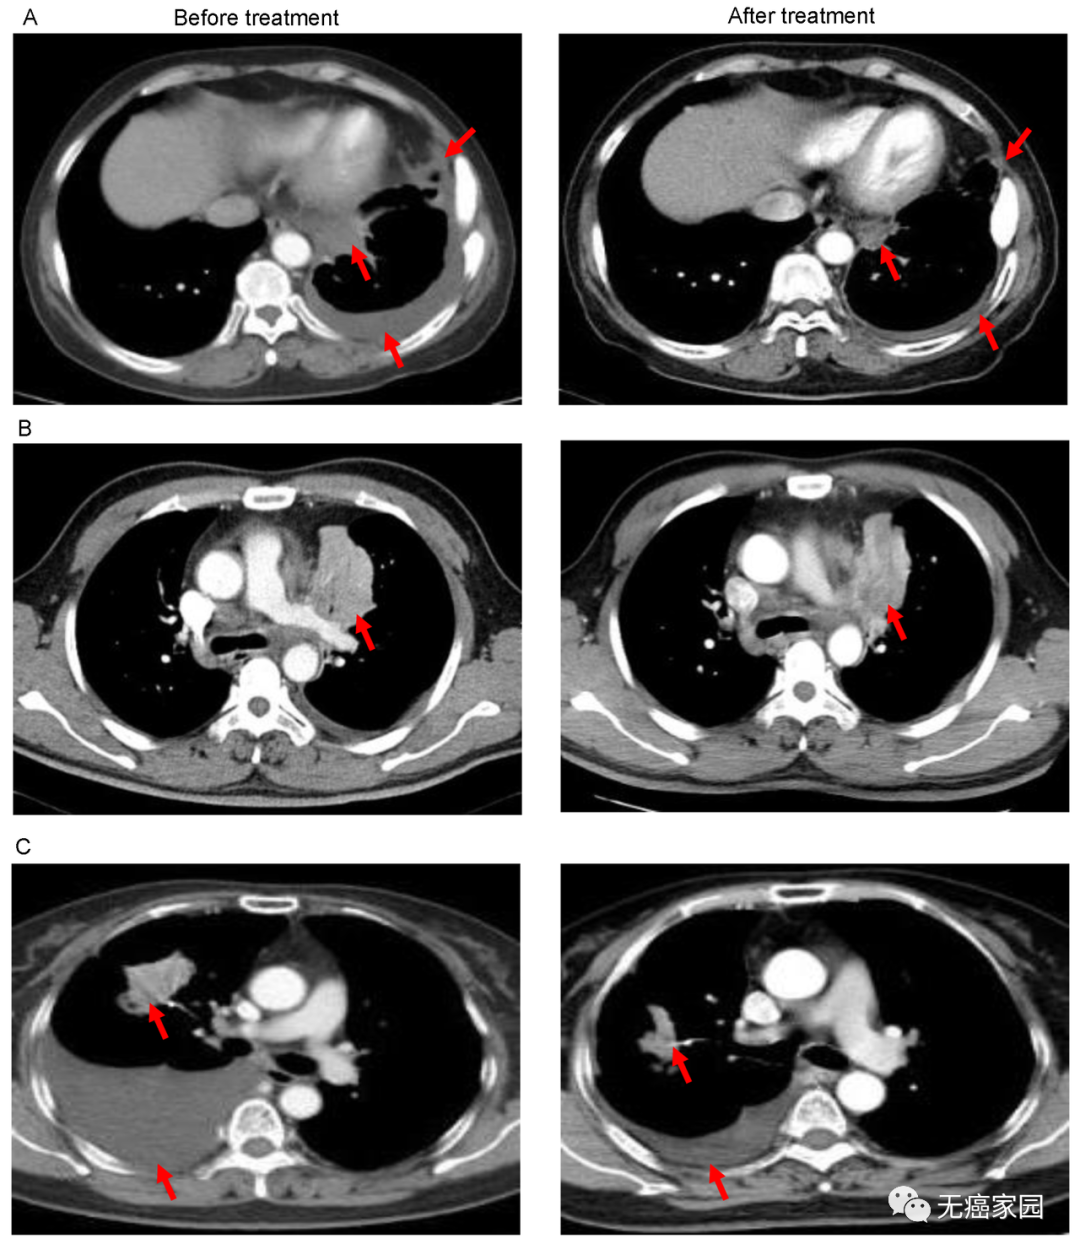

研究结果显示,其中11例患者疗效可评价:2例患者肿瘤明显缩小,5例疾病稳定。

图A中患者1在输注CAR-T细胞后,通过CT扫描显示其胸腔积液减少,转移性肺门淋巴结和胸膜结节轻度缩小(箭头)。

图B中CT图像显示患者8的原发性肿瘤缩小(箭头);

图C中CT检查发现CAR-T治疗后患者9的胸腔积液吸收和肺部病变明显消退。